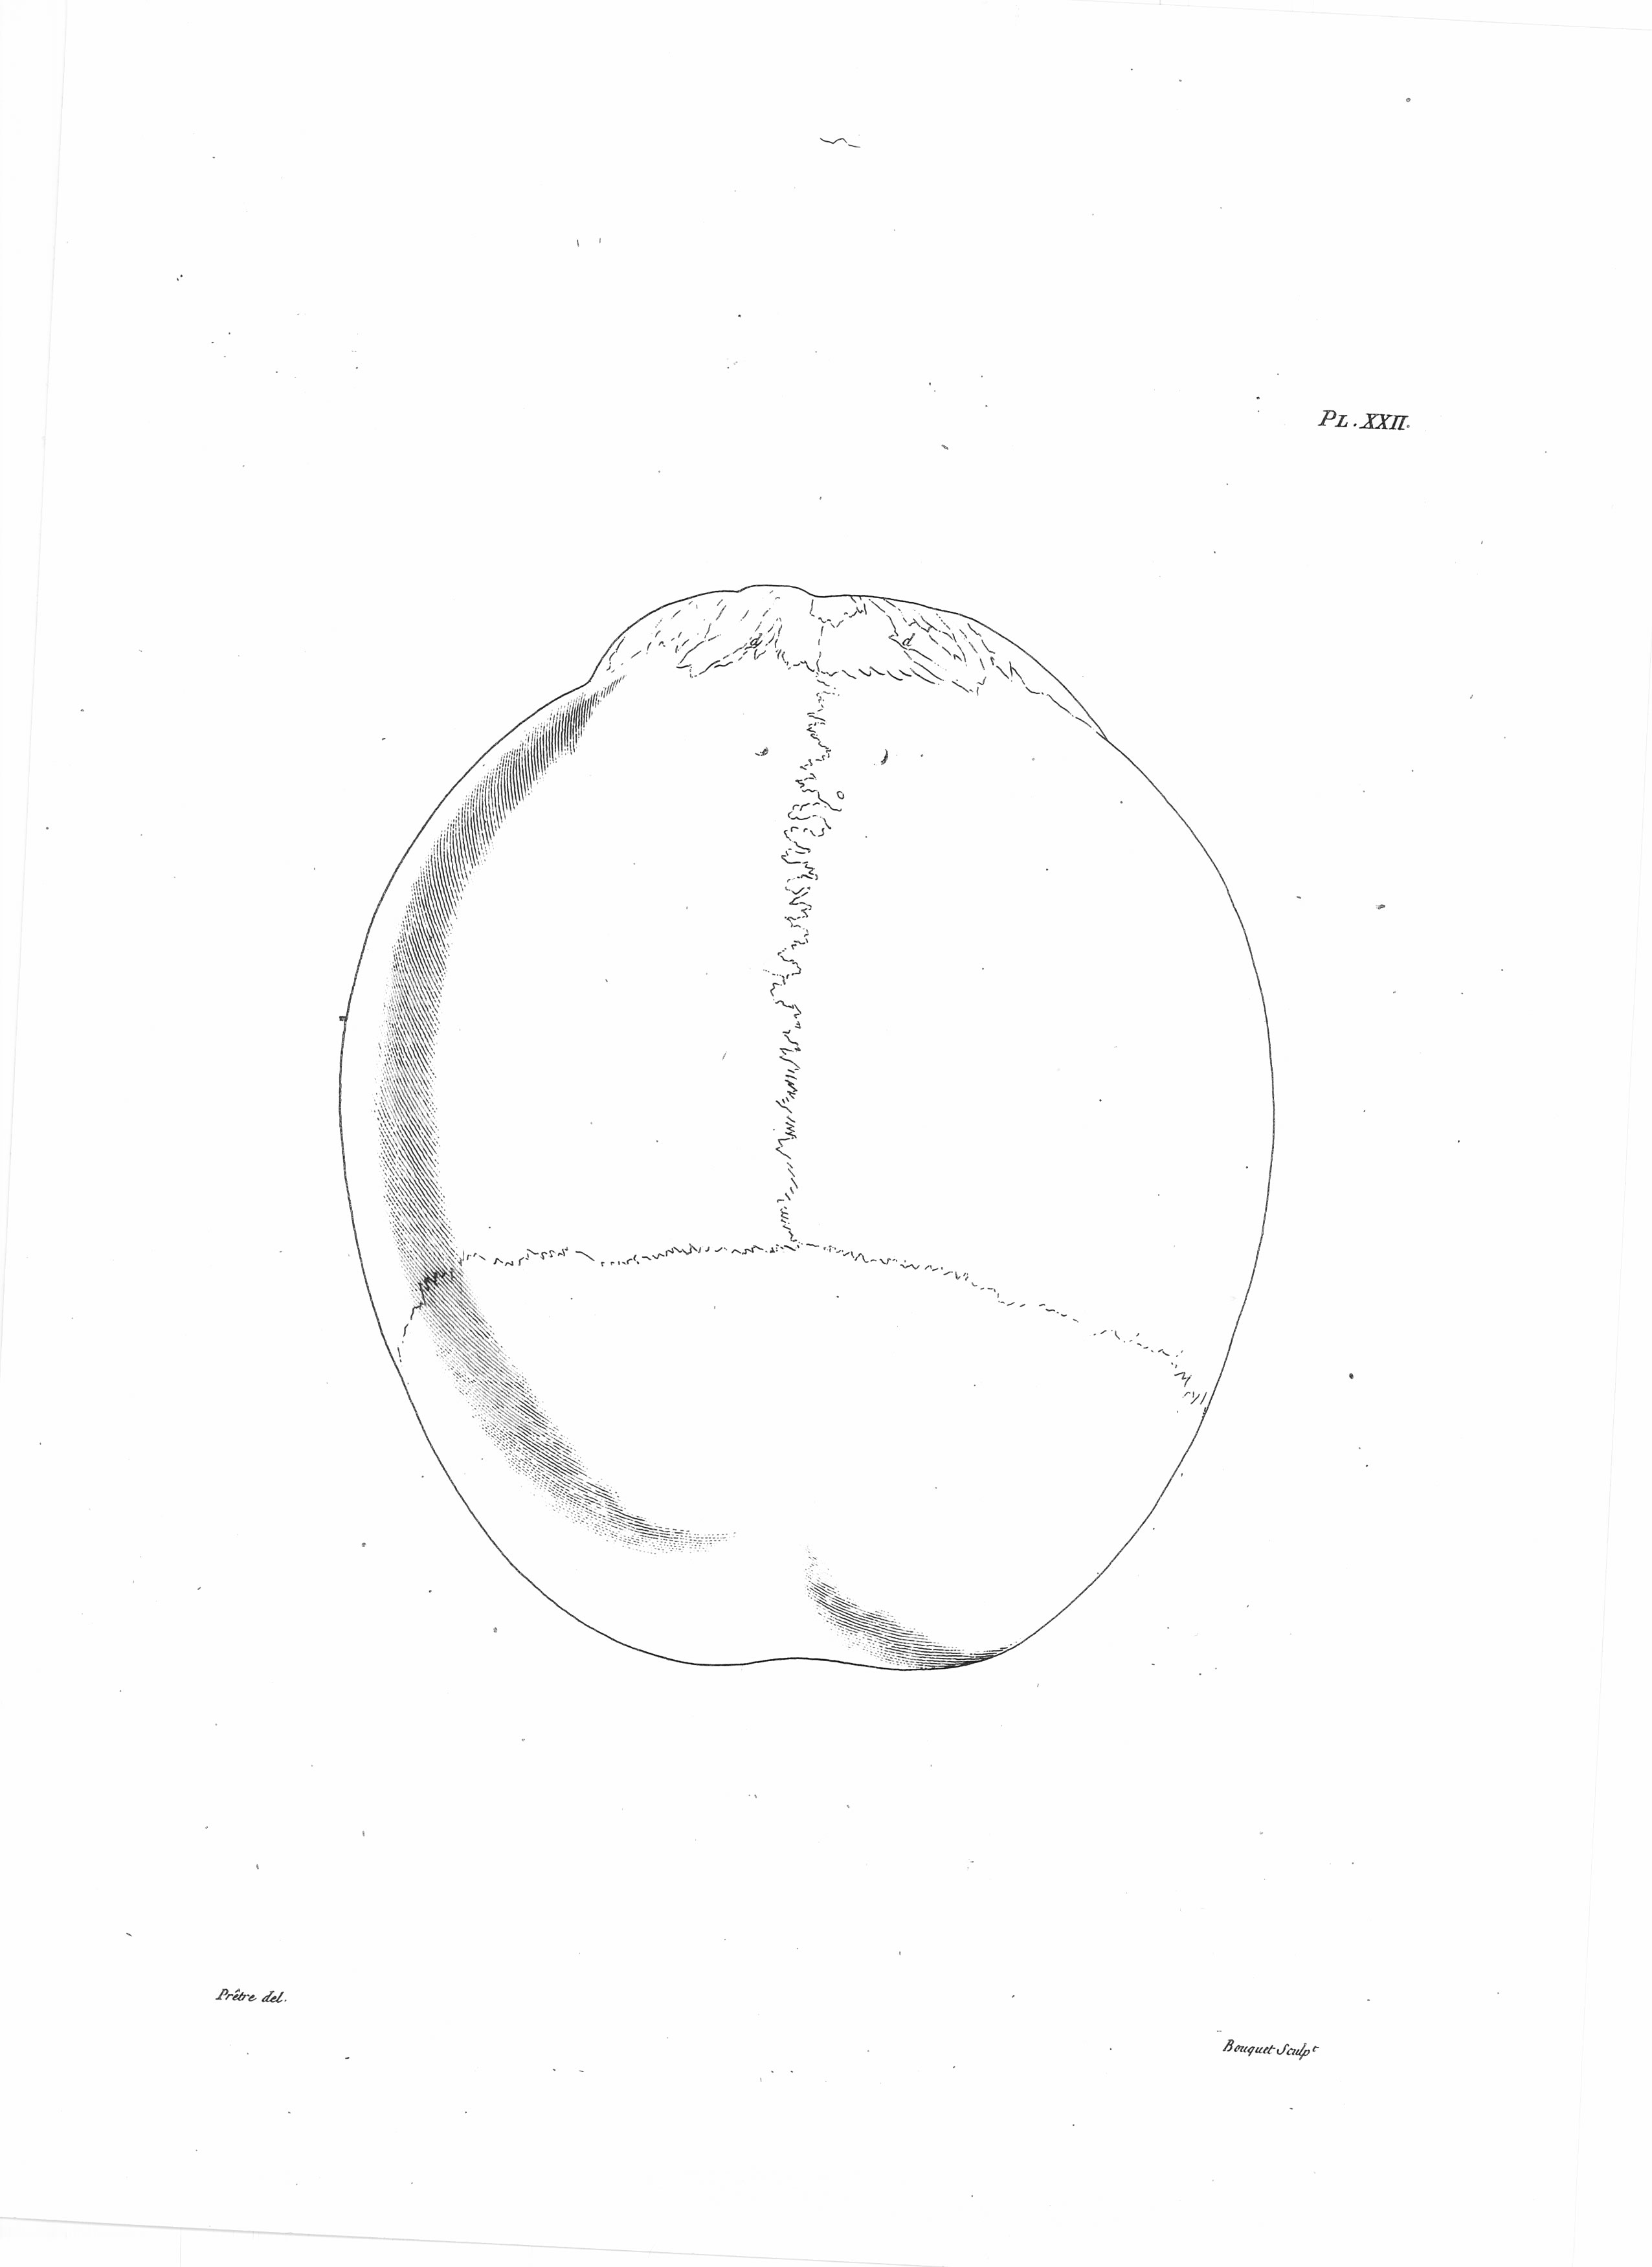

Gall, F. J. (1818). Anatomie et physiologie du système nerveux en général, et du cerveau en particulier, Avec des observations sur la possibilité de reconnoître plusieurs dispositions intellectuelles et morales de l´homme et des animaux, par la configuration de leurs têtes.

Librairie Grecque-Latine-Allemande, Vol. 3, I-XXXV u. 1-379 100 planches.